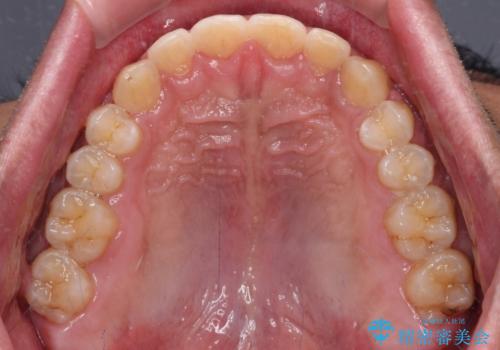

深い咬み合わせと隙間の空いた歯列をワイヤー矯正で改善

- 前歯の隙間と深い咬み合わせを改善したいとのことで来院された患者様です。

奥歯の咬み合わせは理想的な状態であったため、ワイヤー矯正でもインビザラインでも比較的容易に対応可能でした。